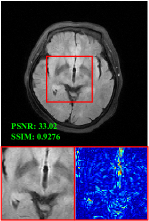

Figure 5 provides the qualitative comparison of the various methods on the four datasets at a scale of 4. The top, second, third, and bottom rows are the SR results under the FastMRI, clinical brain, clinical tumor and clinical pelvic datasets, respectively. The red boxes indicate the zoom-in region of complicated anatomical structures along with their corresponding error maps. Note that the brighter textures in the error maps, the lower the quality of the reconstructed images. As can be seen, compared to methods based on Transformers and CNNs, diffusion-based methods like DisC-Diff and DiffMSR (Ours) are capable of reconstructing high-realistic images with promising reconstruction metric scores (PSNR and SSIM). Nevertheless, while DisC-Diff can reconstruct high-precision MR images, it does not preserve the structure present in the original HR images, introducing some additional information that can affect medical diagnosis. In contrast, our method combines DM and PLWformer, which can preserve the original image’s structure while restoring high-frequency information.